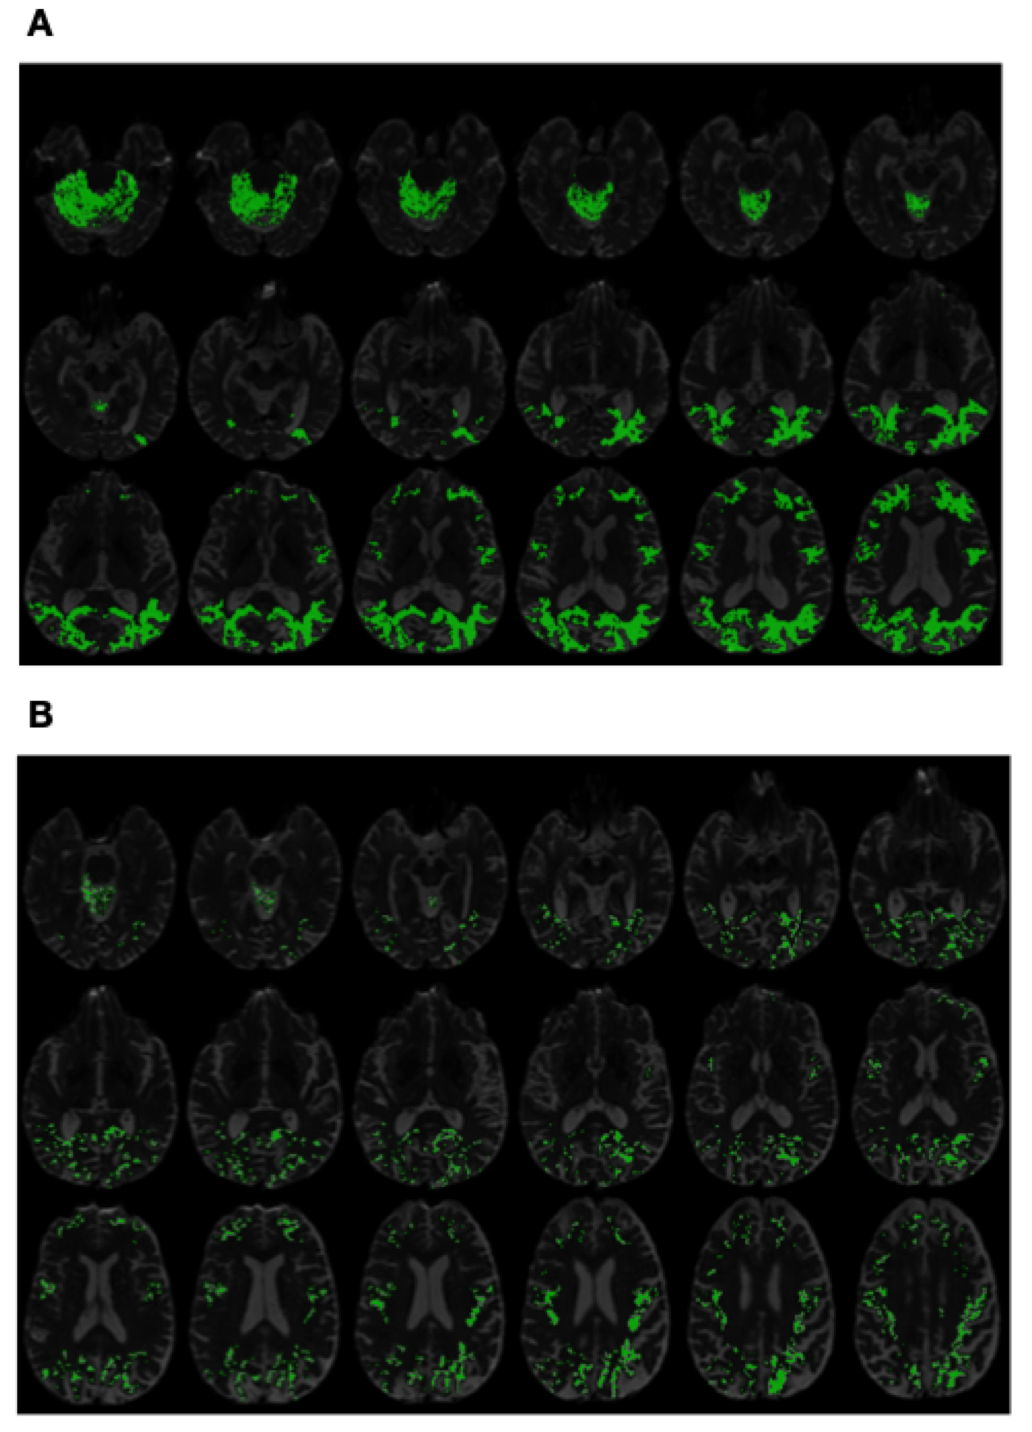

Refer to caption

Figure 5. (Subplot A) PSIC values of an AD subject superimposed on structural MRI scans. (Subplot B) PSIC values of a CN subject superimposed on structural MRI scans.

Finally, Fig. 4 and Fig. 5 exemplify the use of PSIC in its capacity as imaging contrast. It should be emphasized that, as opposed to diffusion metrics, the values of PSIC have no physiological interpretation. Instead, PSIC could be viewed as a pathology-specific risk indicator, whose higher values reflect a higher probability of the brain to be affected by the disease. This property of PSIC is evident in Subplots A of Fig. 4 and Fig. 5 which show the PSIC-enhanced structural scans of two AD subjects. In this case, the spatial distribution of PSIC values appears to be both intense and spatially pervasive. On the other hand, Subplots B of the same figures show results for two CN subjects. One can see that, in this case, the magnitude and spatial spread of PSIC appear to be much more “diluted”.

Due to the preliminary nature of the present paper, an in-detail exploration of the spatial characteristics of PSIC as well as its correlation with underlying brain anatomy and its possible etiological explanations are left beyond the scope of this report. However, in view of the empirical evidence provided by Fig. 4 and Fig. 5, it is reasonable to expect the proposed contrast mechanism to be “worth a thousand words”, both as an adjunct to establishing a confident diagnosis and as a means to facilitate post hoc discoveries.